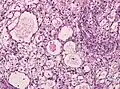

Менинготелиоматозная менингиома состоит из мозаикоподобно расположенных клеток с овальным или округлым ядром, которые содержат умеренное количество хроматина. Строма опухоли представлена немногочисленными сосудами и тонкими тяжами соединительной ткани, которые окаймляют клеточные поля. Характерны концентрические структуры из наслаивающихся одна на другую уплощённых опухолевых клеток. Центр новообразования часто обызвествлён[3].

Фиброзная менингиома состоит из фибробластоподобных клеток, которые располагаются параллельно друг другу и складываются в переплетающиеся между собой пучки, содержащие соединительнотканные волокна. Ядра вытянутые. Могут встречаться концентрические структуры и псаммомные тельца[3].

Переходная менингиома включает элементы менинготелиоматозной и фиброзной менингиом[3].

Псаммоматозная менингиома содержит большое количество псаммомных телец[3].

Ангиоматозная менингиома обильно васкуляризирована, содержит большое количество кровеносных сосудов[7].

Микрокистозная менингиома содержит большое количество микрокист, окружённых опухолевыми клетками звёздчатой формы[8].

Секреторная менингиома является редким гистологическим вариантом данного новообразования. Для неё характерна секреция веществ, которые формируют гиалиновые включения[9].

Менингиомы с обилием лимфоцитов по определению содержат большое количество включений лимфоцитарных масс.

Для метапластических менингиом характерна метаплазия (трансформирование) менинготелиальных клеток в клетки другого типа (к примеру, адипоциты)[10].